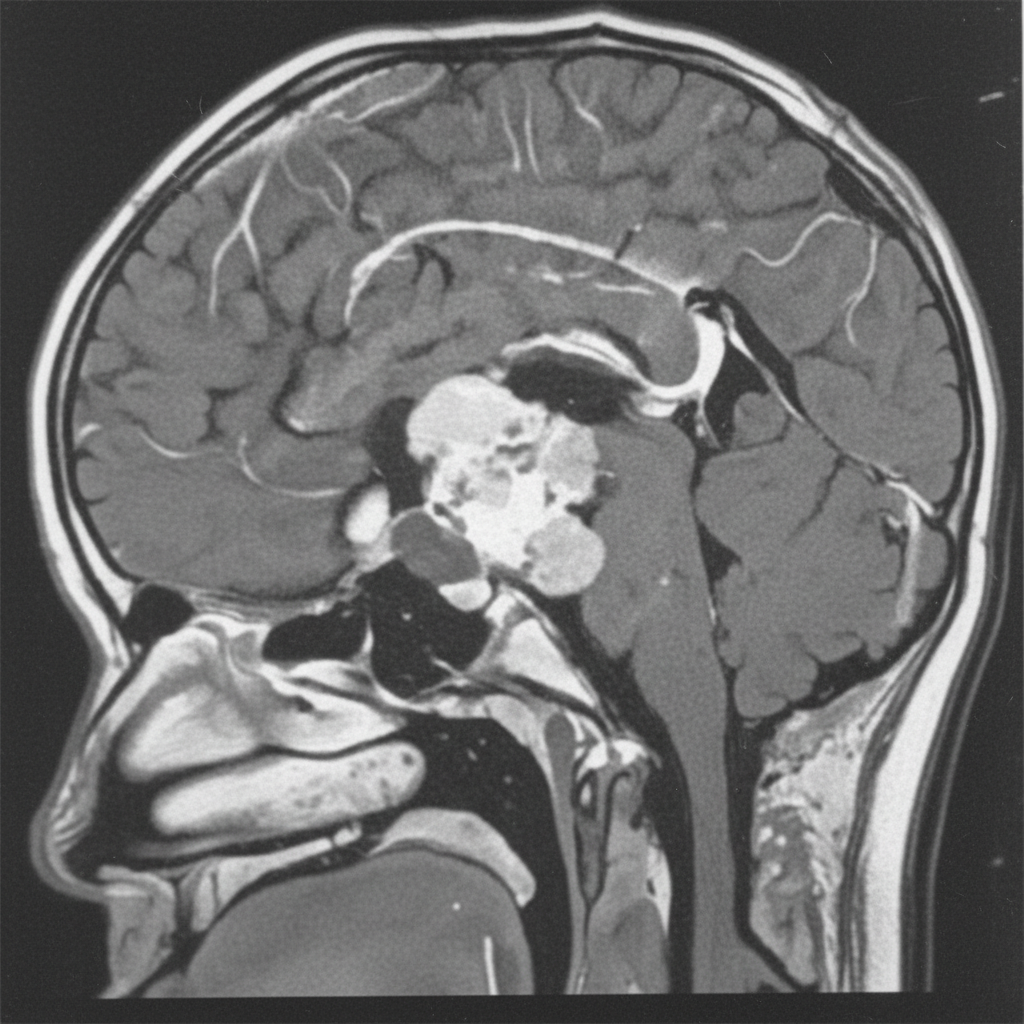

A 12-year-old boy presents with symptoms of headaches, visual disturbances, and growth retardation. An MRI scan is performed, and the image provided shows a cystic mass with both solid and calcified components in the suprasellar region, extending into the third ventricle. Based on the clinical presentation and MRI findings, what is the most likely diagnosis?

Explanation: ***Craniopharyngioma*** - This tumor is classically described as having **cystic** and **solid components** with **calcification**, which is evident in the provided MRI image. Its location in the **suprasellar region** and extension into the **third ventricle** are also typical. - The clinical presentation of **headaches**, **visual disturbances** (due to compression of the optic chiasm), and **growth retardation** (due to hypothalamic-pituitary axis dysfunction) in a 12-year-old boy is highly suggestive of a craniopharyngioma, which commonly affects children and young adults. *Germinoma* - While germinomas can occur in the suprasellar region and cause similar endocrine and visual symptoms, they typically appear as **solid, homogeneously enhancing masses** on MRI and are less commonly cystic and calcified. - They are more common in adolescence and are highly sensitive to radiation therapy, but their imaging characteristics differ from the described lesion. *Meningioma* - Meningiomas typically arise from the **arachnoid mater** and are usually **solid, extra-axial masses** that often have a **dural tail sign** on MRI. - They are less common in children, and while they can calcify, their characteristic imaging features (extra-axial, dural attachment) are not consistent with the described suprasellar, intra-axial cystic mass. *Pituitary adenoma* - Pituitary adenomas originate from the **pituitary gland** and are usually located within the sella turcica, extending superiorly. While they can be cystic, **calcification is rare**, and they are more commonly solid and homogeneously enhancing. - Although they can cause visual disturbances and hormonal imbalances, the prominent cystic-solid appearance with calcification and clear suprasellar origin extending into the third ventricle makes craniopharyngioma a more likely diagnosis in this age group and imaging. *Optic glioma* - Optic gliomas (pilocytic astrocytomas) are common **suprasellar tumors in children**, especially those with neurofibromatosis type 1, and can cause visual disturbances and endocrine dysfunction. - However, they typically appear as **solid, fusiform masses** involving the optic nerve or chiasm with **homogeneous enhancement** and rarely show the characteristic cystic-solid architecture with prominent calcification seen in craniopharyngiomas.